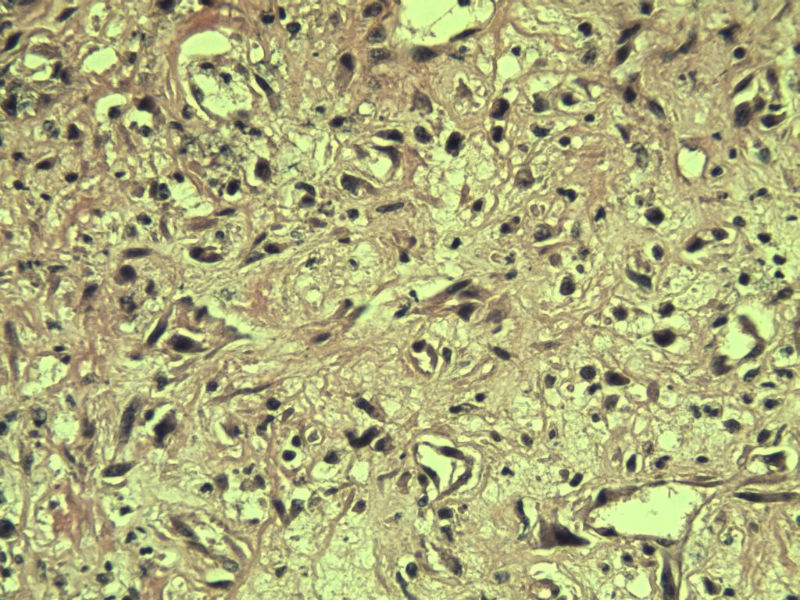

男 33岁 右手食指赘生物5个月 破溃流血一周 灰红不整形组织一块,体积 0.8 × 0.6 × 0.5 cm3。切面灰红,实性,质中。请各位老师看看 是什么? 谢谢了!